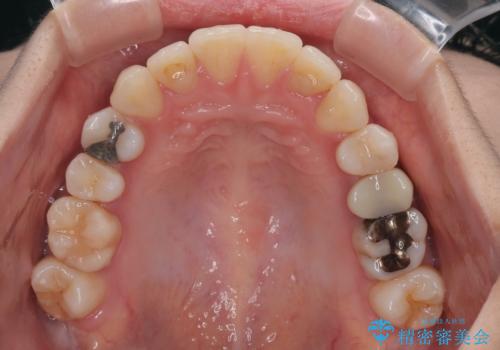

- 上下前歯のデコボコとクロスバイトを気にして来院された患者様です。

治療済みの処置歯が多いため、インビザラインを用いて矯正治療を行うこととしました。

下顎臼歯部にブリッジが装着されており、移動不可のため、IPR(歯と歯の間を削る)と歯列全体を拡大させることで、歯並びを整えていくこととしました。

インビザライン特有の奥歯の噛みにくさが治療後半に発現しましたが、無事に終了させることができました。